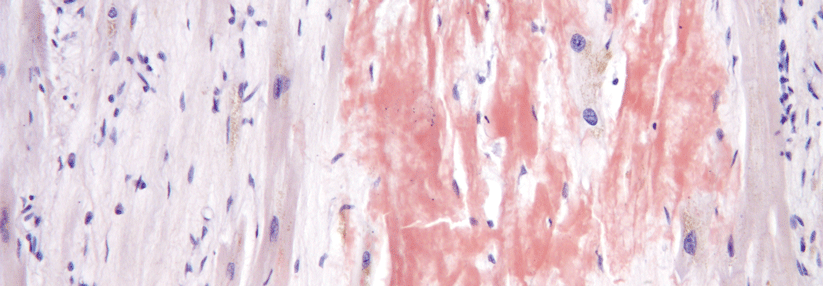

Auch im Gehirn lagert Plaques, der Amyloid-Plaques. Und diese Ablagerungen können dank Antikörper abgetragen werden. Auch im Gehirn lagert Plaques, der Amyloid-Plaques. Und diese Ablagerungen können dank Antikörper abgetragen werden. © fotolia/mrivserg